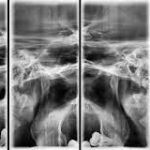

A.T.M. Bilateral BA / BC

Es una técnica mediante la cual, utilizando rayos X, se obtienen imágenes de la articulación temporo-mandibular para su estudio. Indicaciones: traumatismo, dolor al masticar, ruido al masticar, limitación en la apertura bucal.